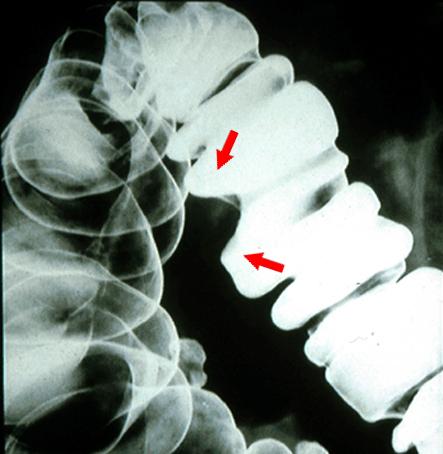

間質にリンパ組織の著明な増生を伴い、粘膜下腫瘍様の所見を呈した進行大腸癌のX線像  腹臥位による大腸の二重造影像で、バリウムを病変部にため、さらに病変を側面像として描出した写真です。病変(矢印)は腸管の陰影欠損像として認められ、変形も伴っています。

疾患(病理主体)の分類悪性上皮性腫瘍/腺癌

部位(臓器別)大腸/横行

腫瘍の肉眼分類2型(潰瘍限局型)/

病変の最大径(ミリ)25〜29

腫瘍の深達度mp